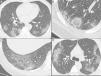

Nonenhanced high-resolution chest CT of different patients with atypical findings. A, 52-year-old man presented with 3-day history of fever, cough and adynamia. Axial chest CT shows centrilobular nodules, tree-in-bud opacities and bronchial mucocele. The patient was diagnosed with pulmonary tuberculosis. B, 26-year-old woman presented with 10-day history of cough, sputum, fever and dyspnea. Axial chest CT shows lobar consolidation. The patient was diagnosed with bacterial acquired community pneumonia. C, 47-year-old woman presented with 30-day history of headache, adynamia, cough and chest pain. Axial chest CT shows pulmonary cavitation with satellite centrilobular opacities. The patient was diagnosed with central nervous system and pulmonary cryptococcosis. D, 55-year-old man presented with 3-day history of orthopnea, precordial pain and cough. Axial chest CT shows bilateral pleural effusion, interlobular septal thickening, and centrilobular ground glass opacities. The patient was diagnosed with congestive heart failure due to myocardial infarction.

Commonly typical features reported in COVID-19 pneumonia were multifocal, rounded and peripheral GGO displaying a sensitivity of 95.3% (95%CI 88.5-98.7), 82.5% (95%CI 72.8-89.9) and 81.7% (95%CI 71.6-89.3), respectively (Table 2; Fig. 3). All patients with atypical appearance (n = 17) on chest CT were not diagnosed with COVID-19 by RT-PCR. Of these, according to their attendant physician, 13 had the final diagnosis of bacterial pneumonia, one had decompensated heart failure and three had no confirmed alternative diagnosis. The most common findings among these patients were centrilobular nodules (n = 15) and tree-in-bud opacities (n = 7) (Fig. 4). Among patients with indeterminate appearance (n = 30), seven had a positive RT-PCR for SARS-CoV-2. In this group, common findings were very few and non-rounded GGO (n = 4), diffuse GGO (n = 2), and unilateral features (n = 1) (Fig. 5). One of them also had radiological features of pulmonary fibrosis.